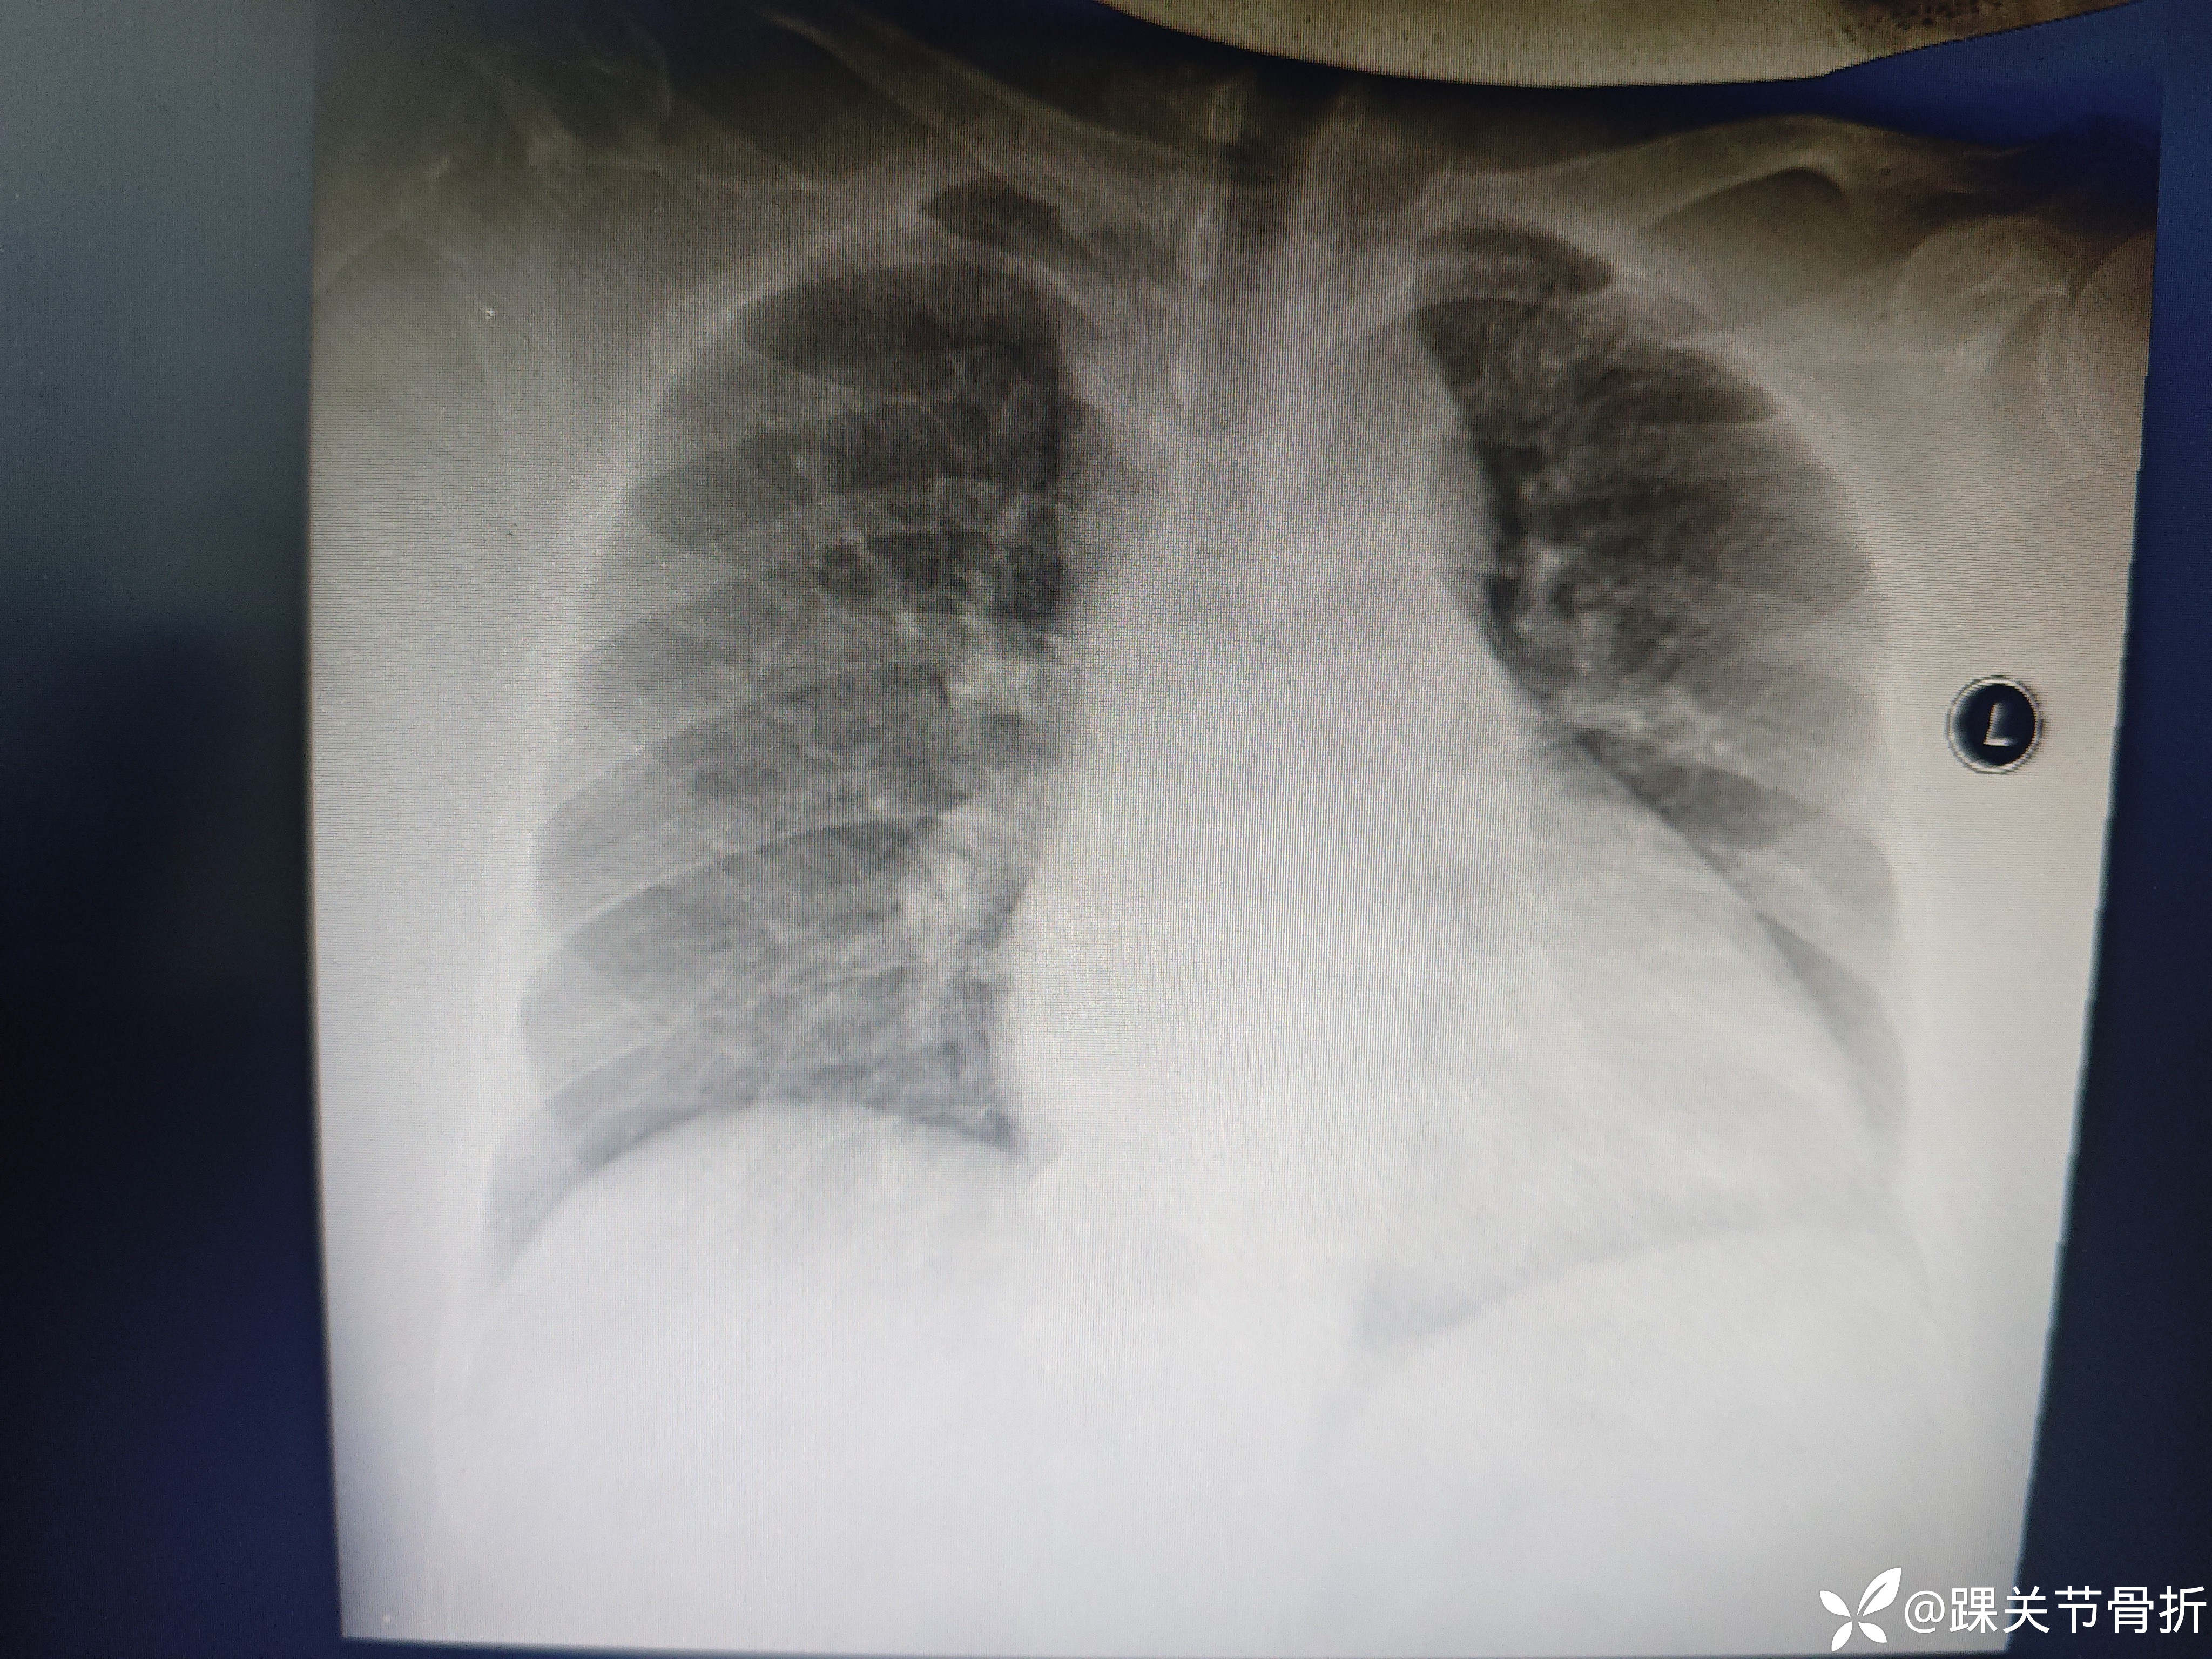

【检查】:9月1日

9月2日

9月3日

10月14日

【治疗经过及结果】:9.1入院骨科完善检查,9.2凌晨体温39.2,检验结果c反应蛋白296.5.b型钠尿肽4761转心内,9.3发热,肝肾功异常,尿量减少血肌酐,尿素升高转肾内,9.4给予头孢哌酮舒巴坦、莫西沙星抗感染及其他对症处理,9.5加用甲泼尼龙抗炎,呋塞米利尿9.12体温正常,9.14体温38,9.17肺炎支原体IGM阳性,应用罗红霉素,布地奈德雾吸9.20

10.2应用阿莫西林克拉维酸钾抗感染,多西环素、萘普生,10.6调整为万古霉素bid加口服利奈唑胺,10.12